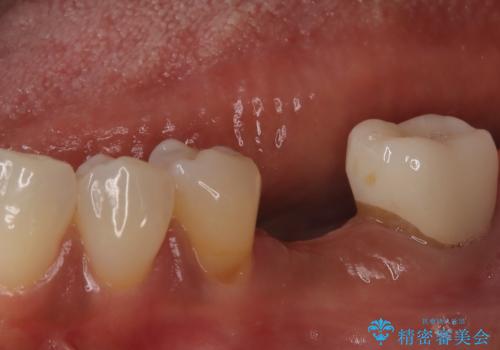

![[ インプラント体・カスタムアバットメント・ジルコニアクラウン ] インプラントの構造の症例 治療前](https://seimitsushinbi.jp/wp/wp-content/uploads/2024/02/d7b3d7509c0cc77833268d7096e1730b-500x350.jpg?v=1708928260)

![[ インプラント体・カスタムアバットメント・ジルコニアクラウン ] インプラントの構造の症例 治療後](https://seimitsushinbi.jp/wp/wp-content/uploads/2024/02/4f5d249988cfa0d7689dd16755d46820-500x350.jpg?v=1708928265)